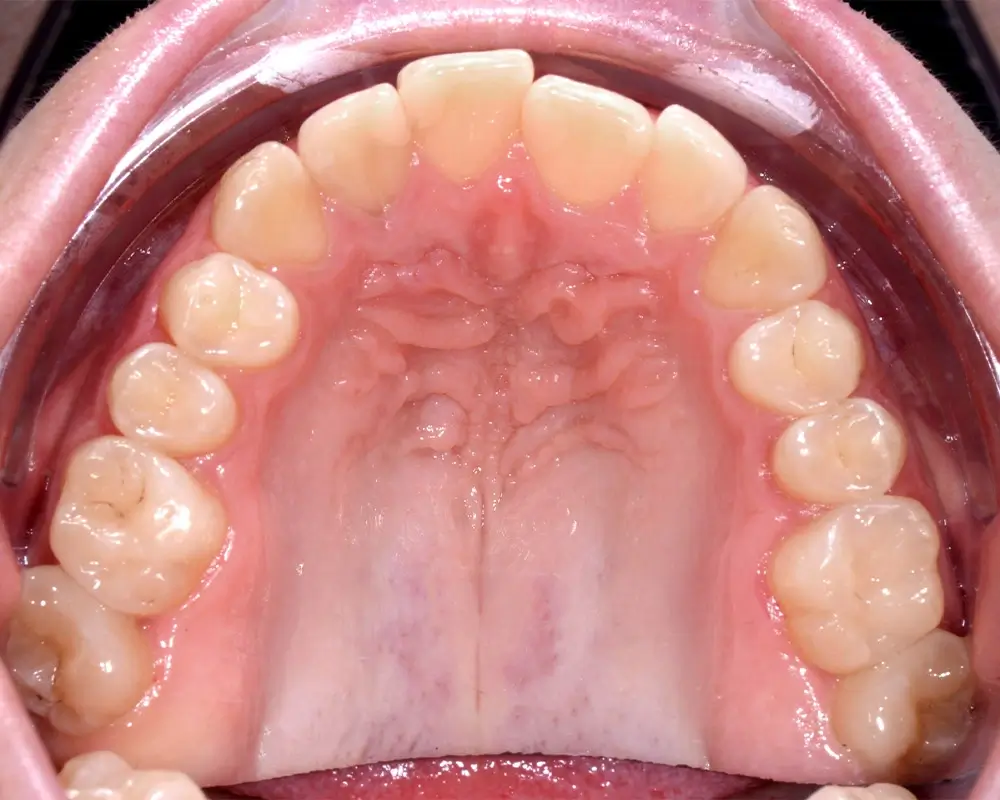

Открытый прикус - Кейс 2

Эффективность устранения дефекта прикуса посредством элайнеров FlexiLigner.

Результаты лечения